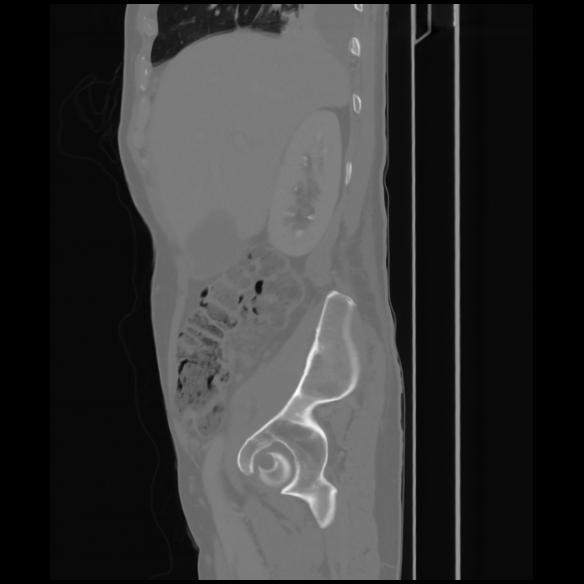

7 CUERPO,CE,Sagittal,3.000,CUERPO,Sagittal,